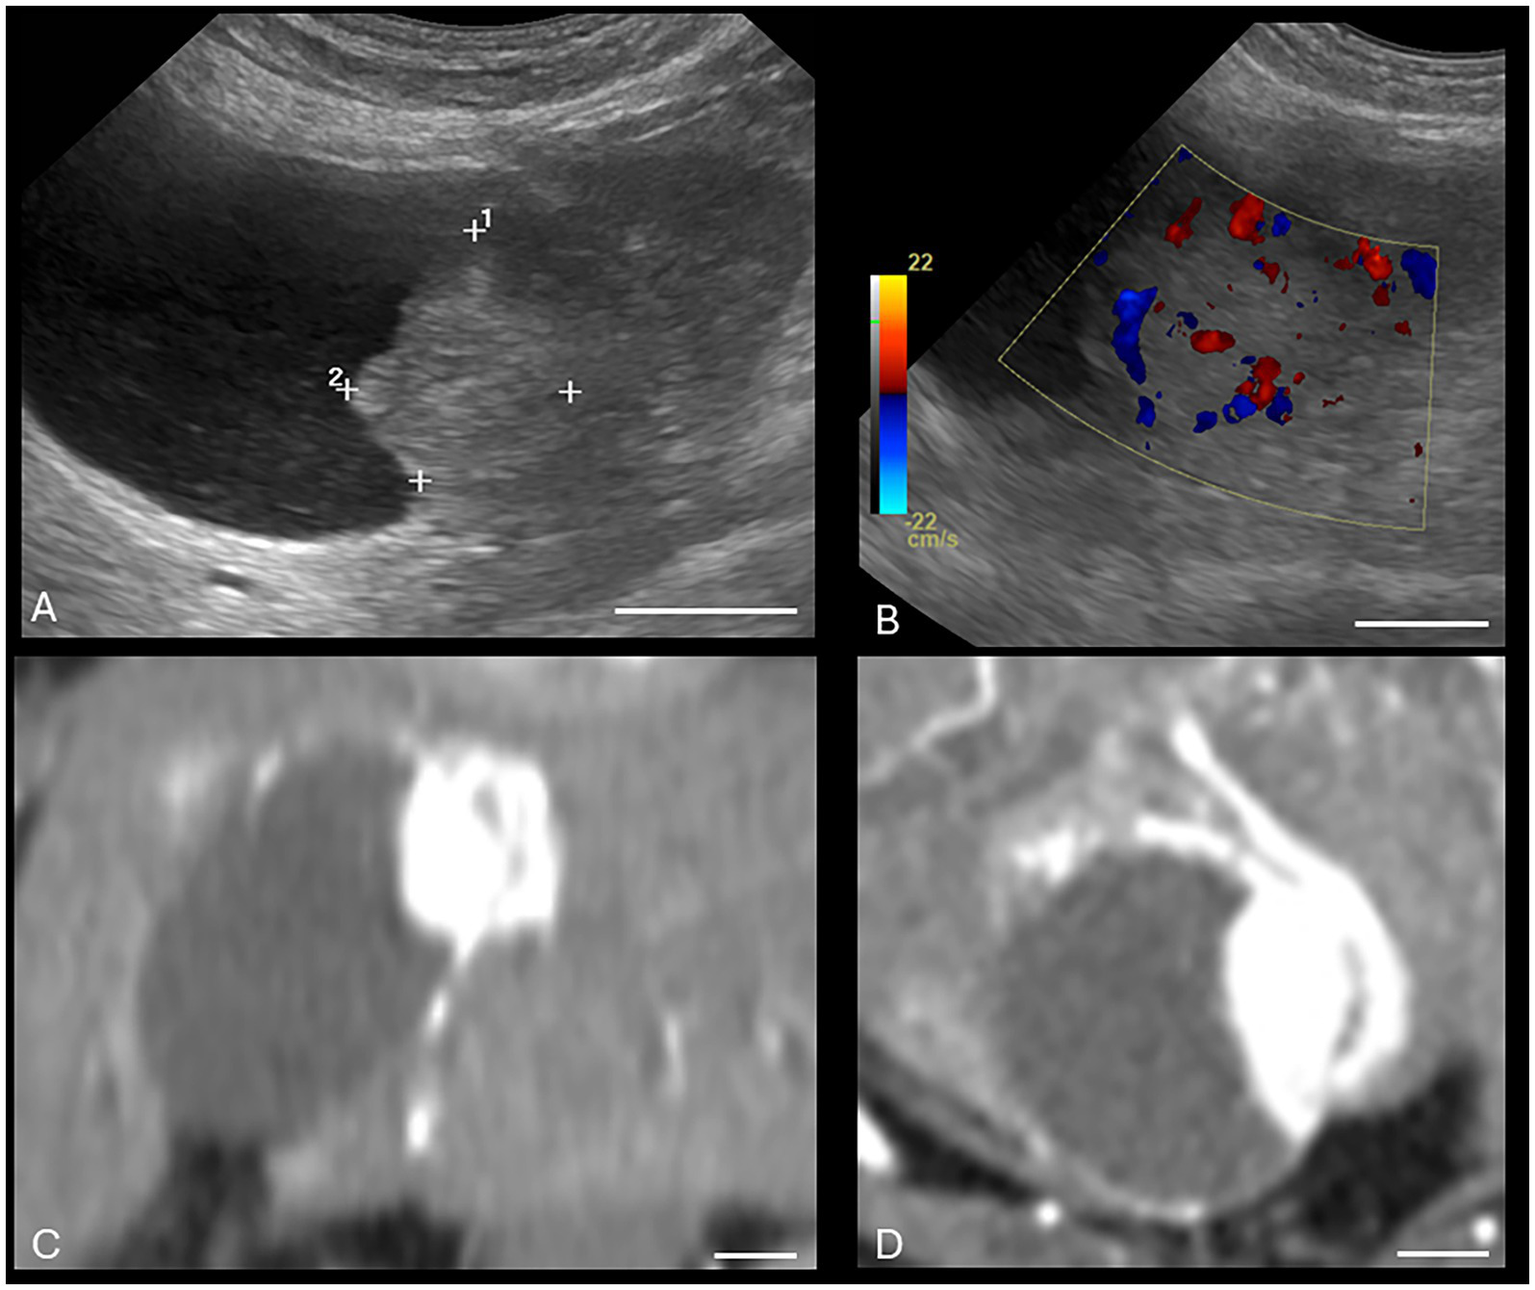

Both US and CT successfully identified the one gallbladder wall mass (malignant carcinoid) (Figure 1). Ultrasound and CT performed equally well in identifying all six gallbladder mucoceles, with no discordant pairs and an ICC of 1.0 (Figure 2). The imaging characteristics of all gallbladder mucoceles were consistent with those previously described (8–10).

Figure 2. Canine gallbladder mucocele on CT and US. (A) Transverse B-mode ultrasound image of the gallbladder. There is central stellate hyperechoic intraluminal material, consistent with a gallbladder mucocele. There is additionally gallbladder dilation, a thickened and hypoechoic gallbladder wall, small volume surrounding peritoneal free fluid, and hyperechoic mesentery, consistent with peritonitis and concerning for gallbladder rupture. (B–D) Transverse soft tissue window (WW = 400, WL = 50) precontrast (B), post-contrast arterial phase (C), and venous post-contrast (D) CT images of the same patient. There is severe gallbladder dilation and central hyperattenuating material. The white calibration bar at the bottom right of each panel delineates 1.0 cm.